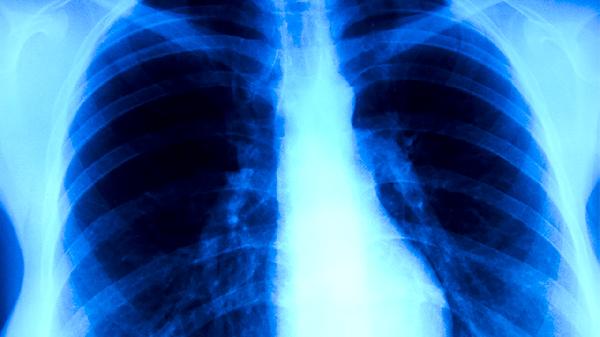

患者住院48小时后出现咳嗽、咳痰或原有呼吸道症状加重是常见表现,痰液可能呈黄绿色或铁锈色。听诊可闻及湿啰音或支气管呼吸音,部分患者伴随胸痛或呼吸困难。胸部X线或CT检查显示新发斑片状浸润影,多分布于肺下叶。血常规检查可见白细胞计数升高或降低,中性粒细胞比例增高,C反应蛋白和降钙素原等炎症指标上升。痰培养、血培养或支气管肺泡灌洗液检查可明确病原体,常见致病菌包括铜绿假单胞菌、肺炎克雷伯菌和金黄色葡萄球菌。